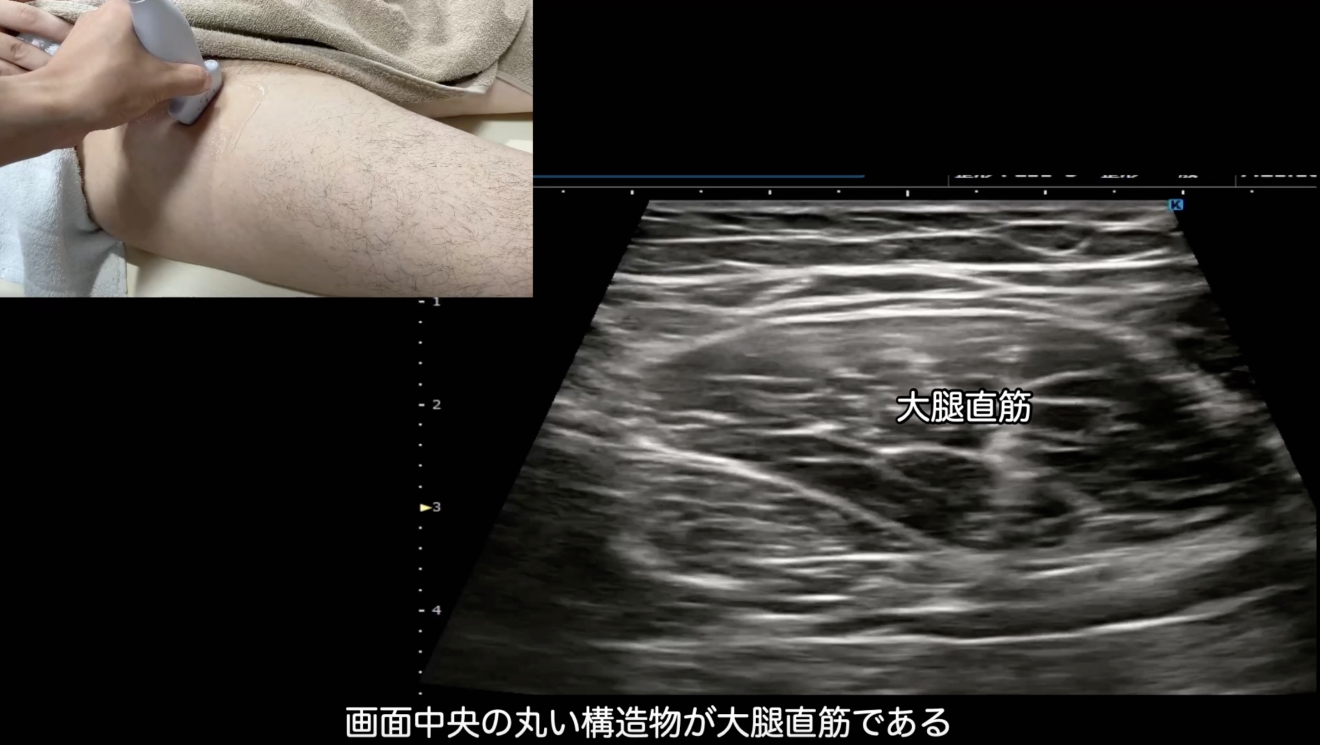

✅ 股関節前面の解剖復習

*恥骨筋・大腿直筋・大腿直筋下脂肪体・大腿神経・腸腰筋・縫工筋・大腿筋膜張筋

✅ エコーの基本的な使い方

*プローブの走査・画像の見方